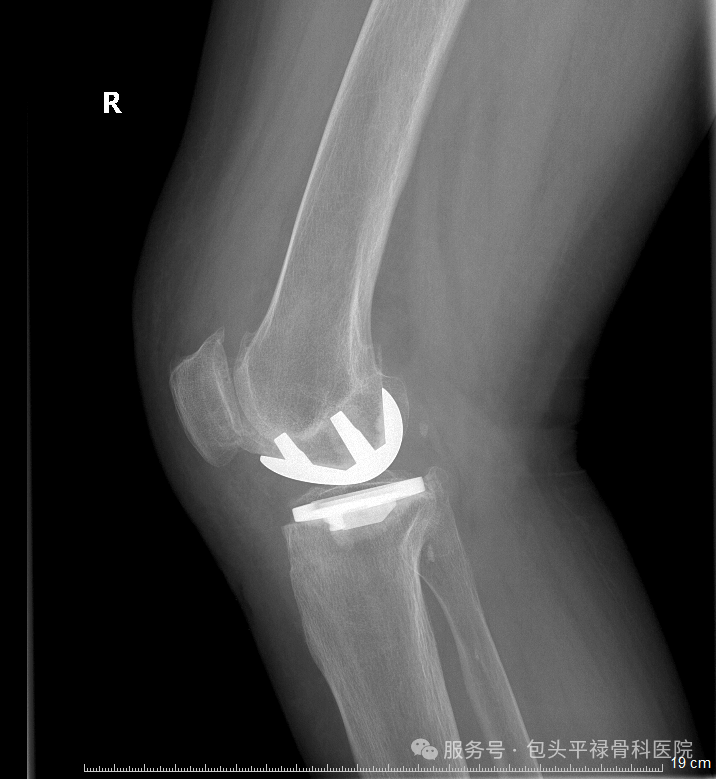

膝关节单髁置换术相当于“局部翻新”,就是只置换“坏掉房间”的磨损表面,仅将受损的软骨和部分骨质去除,替换为人工假体,而完好的软骨、交叉韧带及其他结构都得以最大程度的保留。

关节炎主要局限于膝关节的一个间室,其他间室和髌股关节软骨基本完好。

膝关节的前后交叉韧带、内外侧副韧带结构完整,功能良好。这是保证手术效果和关节稳定性的关键。